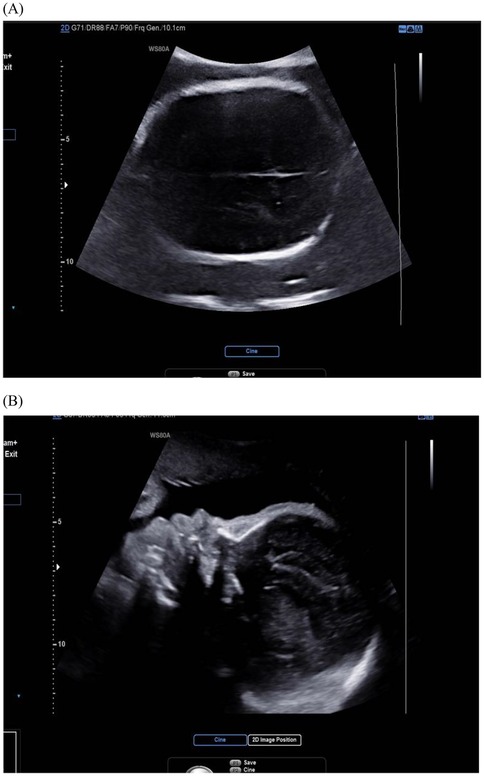

Bicoronal suture fusion constitutes the pathognomonic cranial hallmark of Apert syndrome, detectable sonographically from 18 gestational weeks. The most recognized manifestation is turribrachycephaly, characterized by a cranial index exceeding 90% (specificity 94%) and an abnormal fronto-occipital to biparietal diameter ratio >0.72, resulting in a towering cranial vault with frontal bossing (14). Crucially, modern ultrasound protocols now prioritize sutural biomarker analysis over isolated morphology assessment. Absence of the normal hypoechoic suture line, coupled with aberrant Doppler flow signals at coronal sutures, provides direct evidence of synostosis, reducing false positives from positional molding (10) (Figure 1).

Ultrasound images of the fetal skull in Apert syndrome. (A) Cross-sectional view showing fusion of the coronal suture, which is not visible due to synostosis. (B) Midsagittal view demonstrating an abnormal skull shape with a protruding forehead.

Figure 1. Ultrasound image of fetal skull in Apert syndrome: closed coronal suture (cross-section) and frontal bossing. (A) Cross-section view: the coronal suture, as seen in the cross-section of the skull, is closed and therefore not visible; (B) midsagittal view: the skull shape is abnormal, with a protruding forehead.